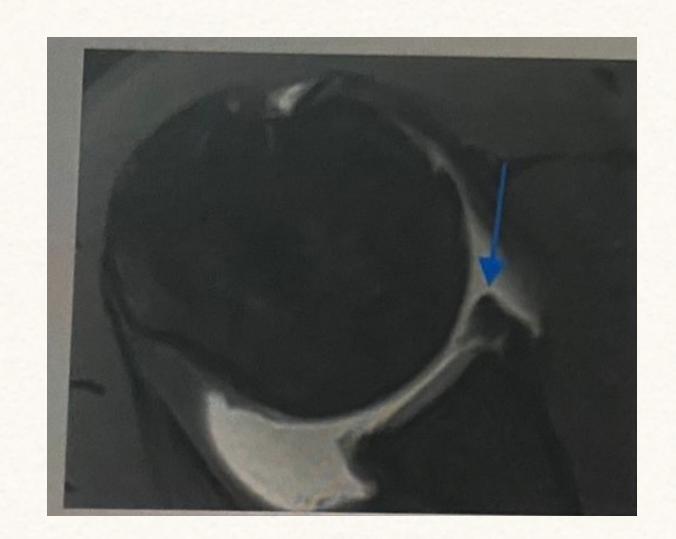

Meniscal Tear Identification

What pathology is seen in this MRI of an 18-year-old male who twisted his knee?

- Posterior horn meniscal tear

- Bucket-handle meniscal tear

What is the significance of the double PCL sign?

- Indicates bucket-handle meniscal tear

What does the white arrow indicate in this image?

- Posterior meniscus horn

What is the diagnosis shown in these images?

- Posterior meniscus horn tear